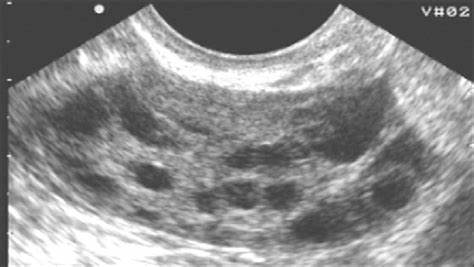

Картинка 59: Узи Яичника Фото — Картинки фотографии